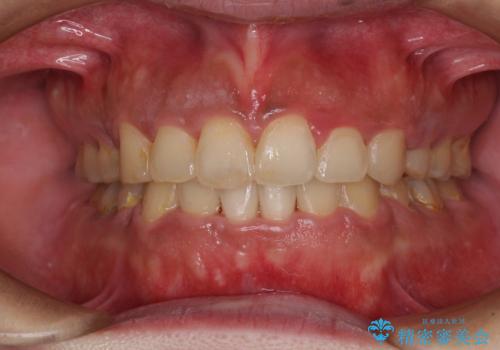

- 上下前歯のデコボコを気にして来院された患者様です。

上顎歯列が下顎の歯列に対して狭小であり、一部下顎の奥歯が上顎よりも外側に位置している状態でした。

上顎の急速拡大装置を使用して上顎骨を側方に拡大することで上顎歯列を拡大し、下顎歯列も拡大できるようにすることで、歯列を整えることとしました。

歯列矯正では基本的に骨格を改善することはできませんが、急速拡大装置(MARPE)を使用することで上顎骨を側方に拡大させることができ、咬合状態を大きく改善することができます。